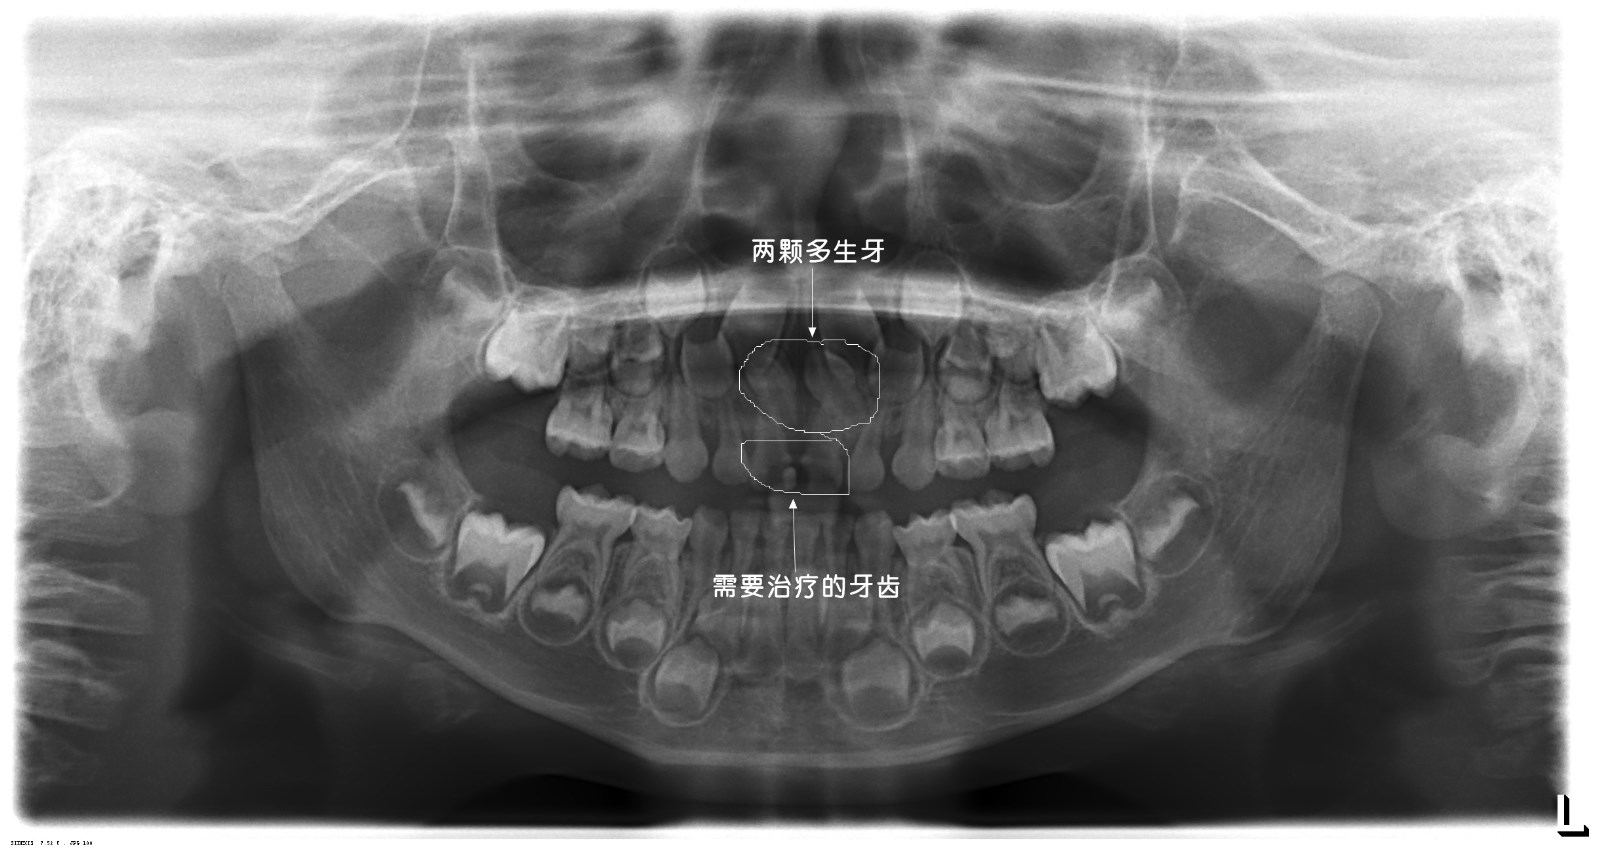

近日,一名门牙疼痛不适患儿就诊我院口腔科,临床检查发现患儿上颌两颗乳中切牙曾于外院充填治疗(补牙),其中一颗急性根尖炎(蛀牙导致牙神经坏死继而根尖发炎)导致了患儿不适。影像学检查发现乳牙根方两颗多生畸形小牙,存在于继替恒牙萌出路径上。口腔科医生首先给予主诉牙开髓引流(消炎),发现患儿极其恐惧口腔治疗,遂与患者家长充分交流沟通决定全麻下治疗两乳牙同时拔除两颗埋植于颌骨内的多生牙。

在麻醉医师精准的麻醉配合下,两颗乳牙的治疗及两颗多生牙的拔除快速高效的完成。这一切均发生在患儿“熟睡”的情况下。术毕,停药,患儿复苏,观察,回家。两颗发炎的乳牙已完成治疗并焕然一新,两颗“恼人”的多生牙已告别小主人。